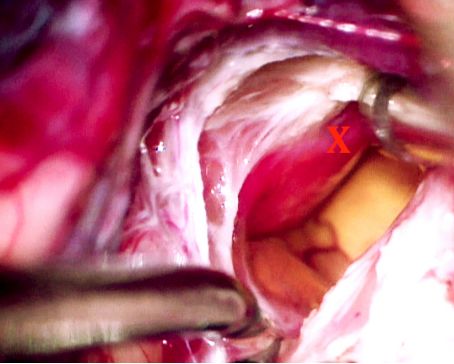

实质性HB通常需要更细微、合理的入路进行操作,其操作流程与富血供的AVM手术类似,肿瘤内部有许多容易出血的微小血管,因此难以用双极电凝进行止血,这个特性让手术切除带来极大的风险,因此不应尝试分块切除。

彻底止血在手术操作过程中至关重要,能够避免术中患者失血过多。术中最好能早期发现供血动脉并立即阻断,但对脑干病变,术者并不总能实现这一目标,尤其当病变内侧有来自硬膜和软膜的血供时,会给术者带来不少麻烦,因此强烈术前进行供血动脉栓塞。如果病变区域的重要血管阻断后,有可能引起小脑肿胀,因此对巨大HB而言,建议分次进行手术是合理的。

大的引流静脉一般位于结节的表面,轻微触碰这些静脉可以导致其破裂大出血,因此控制这些静脉极具挑战性。如果阻断了引流静脉,将会引起HB内部的血流动力学变化,导致更多的出血,引起恶性循环,因此具有极大的风险。笔者再次强调,术前进行供血动脉栓塞并在手术早期对供血动脉进行离断很重要。这样策略性的操作有助于手术成功。

对位于脑干重要结构附近的HB进行分块切除以获取更多空间是不可行的,通过阻断供血动脉来肿块的才是合理的手术策略。